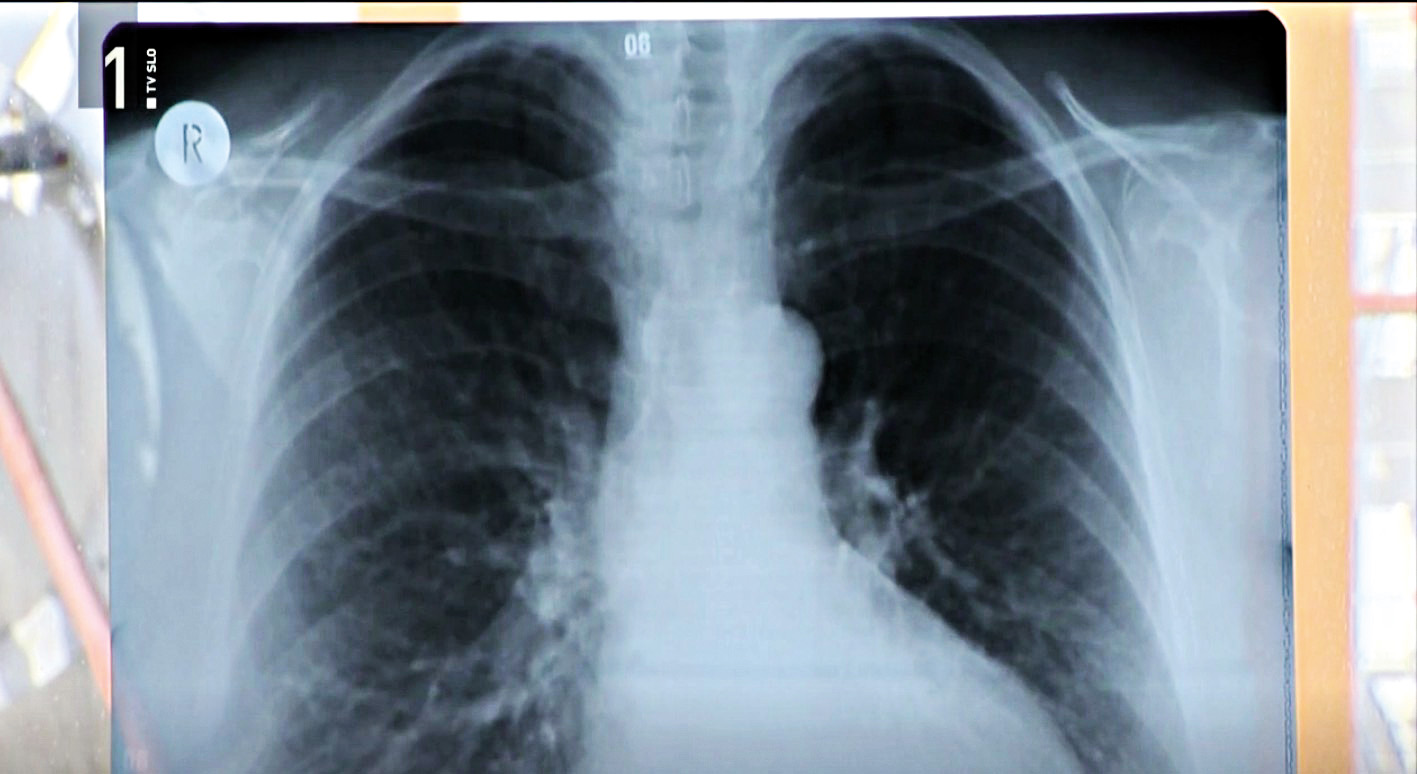

V 20 letih so odkrili kar 450 primerov raka, z azbestom je povezan zlasti rak pljučne in trebušne mrene (na sliki).